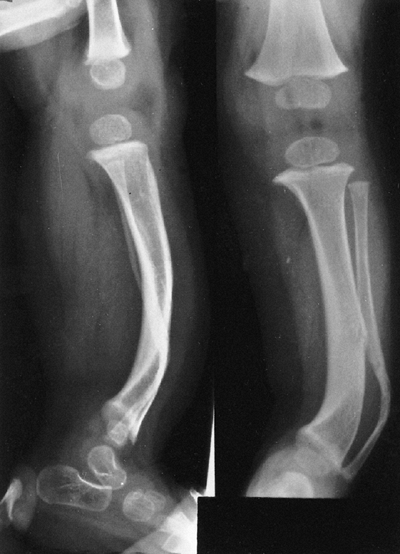

findings that include nail dysplasia, patellar hypoplasia, elbow

dysplasia, and iliac horns (183). The most prominent feature is dystrophic nails (Fig. 9.17A). The nail may be completely absent, hypoplastic, or have grooves and distortions in its surface (184).

The thumb is more involved than the small finger, and the ulnar border

more involved than the radial. The hands are often very symmetric, and

fingernails are more involved than toenails.

Where present, they are unstable, and may be found in a position of

fixed dislocation. The patellar abnormality highlights the total knee

dysplasia, with an abnormal femoral condyle and a peculiar septum

running from the patella to the intercondylar groove (septum

interarticularis), dividing the knee into two compartments.

Abnormalities in varus and valgus alignment occur, with valgus more

common because of the small, flat lateral femoral condyle (185).

The elbow joint is dysplastic, with abnormalities in the lateral

humeral condyle, in many ways mimicking the dysplasia of the knee. The

trochlea is large and the capitellum is hypoplastic, creating an

asymmetric shape that may predispose the radial head to dislocation.

common (Fig. 9.17B). An intraarticular septum makes arthroscopic management difficult, but the septum can be removed arthroscopically.

Figure 9.17 Nail-patella syndrome. The classic quartet of features consists of dystrophic nails (A), absent patellae (notice the region of osteochondritis dissecans on the lateral film) (B), posterior dislocation of the radial head (C), and iliac horns (D).